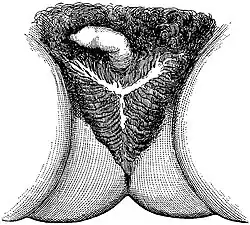

There were two kinds of castration: the "lesser seal" and the "greater seal". For men, the "lesser seal" meant the removal of the testicles only, while the "greater seal" involved either removal of the penis or emasculation (removal of both penis and testicles). Men who underwent the "greater seal" used a cow-horn when urinating. The castrations and emasculations were originally performed with a red-hot iron, called the 'fiery baptism'. However, the skoptsy later transitioned to using knives or razors, with the iron serving only to stop the bloodflow. They also twisted the scrotum, destroying the seminal vesicles and stopping the flow of semen.

In women, the Skoptsy removed the nipples or the whole breasts. Occasionally, they simply scarred the breasts. They also often removed the labia minora and clitoris. They did not use anesthetics.[3]